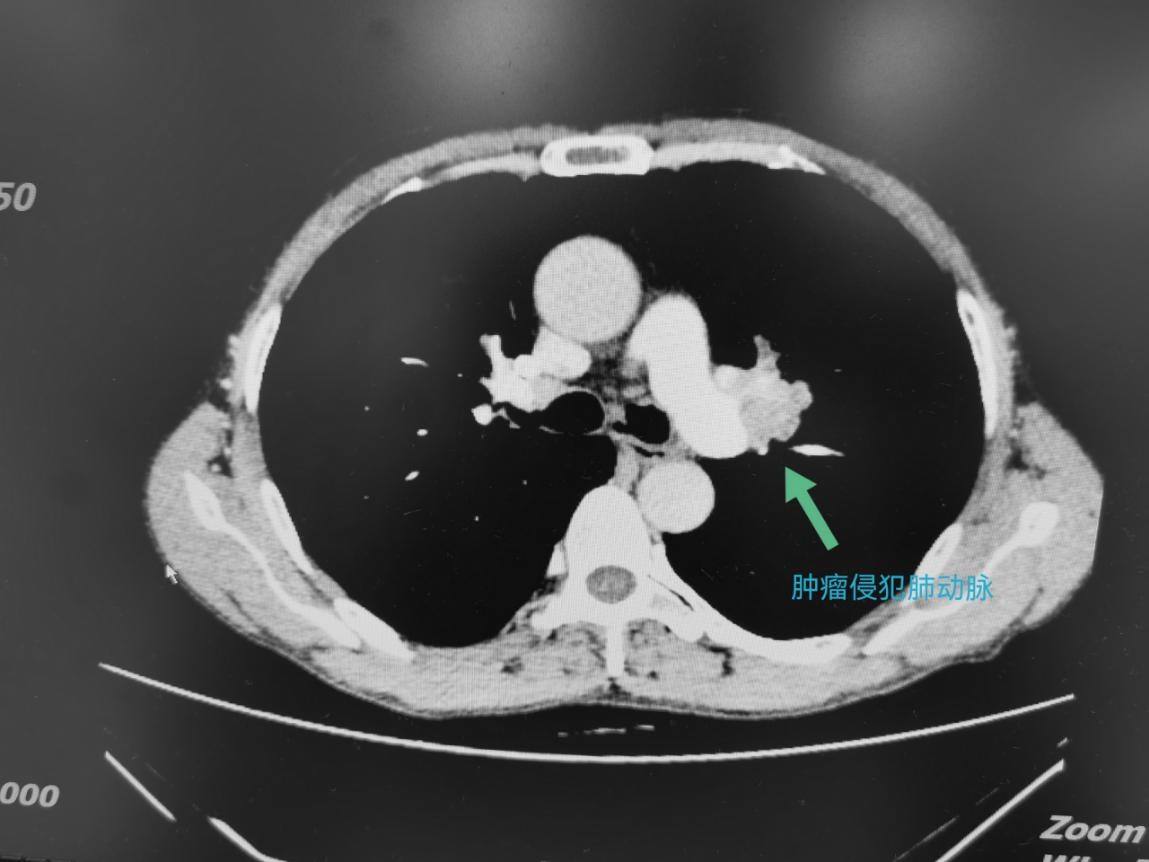

因为咳痰带血,65岁的刘爷爷来到成都市第三人民医院普胸外科就诊。“医生,快点帮我看下是啥问题,我还赶着回家收花生呢。”对于自己的病情,没有其他不适感的刘爷爷很乐观,认为“问题绝对不大”。然而,检查结果却很糟糕——左肺肺门区长了一个直径约4.5cm的肿瘤,并且肿瘤已经侵犯到肺动脉主干和支气管,经过病理检查证实为肺鳞癌。唯一说得上幸运的是,没有发现远处脏器有转移灶。

新辅助治疗前